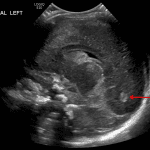

Age: 4 days (born at 24 weeks)

Sex: Male

Indication: Evaluate for germinal matrix hemorrhage

Grade 2 germinal matrix hemorrhage

Sample ReportLeft germinal matrix hemorrhage involving the caudothalamic groove and layering in the occipital horn of the left lateral ventricle without hydrocephalus (grade 2).

No abnormal brain parenchymal echogenicity or extra-axial collections.

Premature sulcation pattern.